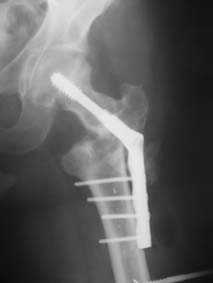

Leonid Solomin 03 Март 2009, 22:07

Уважаемый Попов Виктор!

Возможно, пример (в приложении) поможет Вам определиться с выбором тактики лечения (у нашего пациента, кроме тугого ложного сустава вертельной области, сложная деформация н/3 бедренной кости; т.к. это не имеет значения к обсуждаемой теме - оставил "за кадром"). Как Вы видите, мы в данном случае не вводили чрескостные элементы в зону установки имплантата. При отказе от наложения опоры на таз (кстати, она не обязательно может быть громоздкая спицевая; арки со стержнями-шурупами, введенными в крыло подвздошной вполне достаточно) "не удивляйтесь", если опора со стержнями-шурупами, введенными в вертельной области в скором времени дестабилизируется, возникнет воспаление мягких тканей у чрескостных элементов. Такая опора "имеет на это право": нагрузка конечности от вершины дистального фрагмента до кончиков пальцев ляжет на нее. А двух-трех введенных рядом стержней-шурупов, как их не разноси от фронтальной плоскости, в данном

случае явно недостаточно для адекватной фиксации. + для того, чтобы выбрать оптимальные чрескостные элементы для промежуточной и дистальной опор, можете воспользоваться атласом

В приложении пример пациента, близкого по картине к тому, что представил Виктор (варус и смещение периферического отломка на поперечник кзади). Сделали как раз то, что Виктор исходно намеревался - аппаратная коррекция и затем гамма.